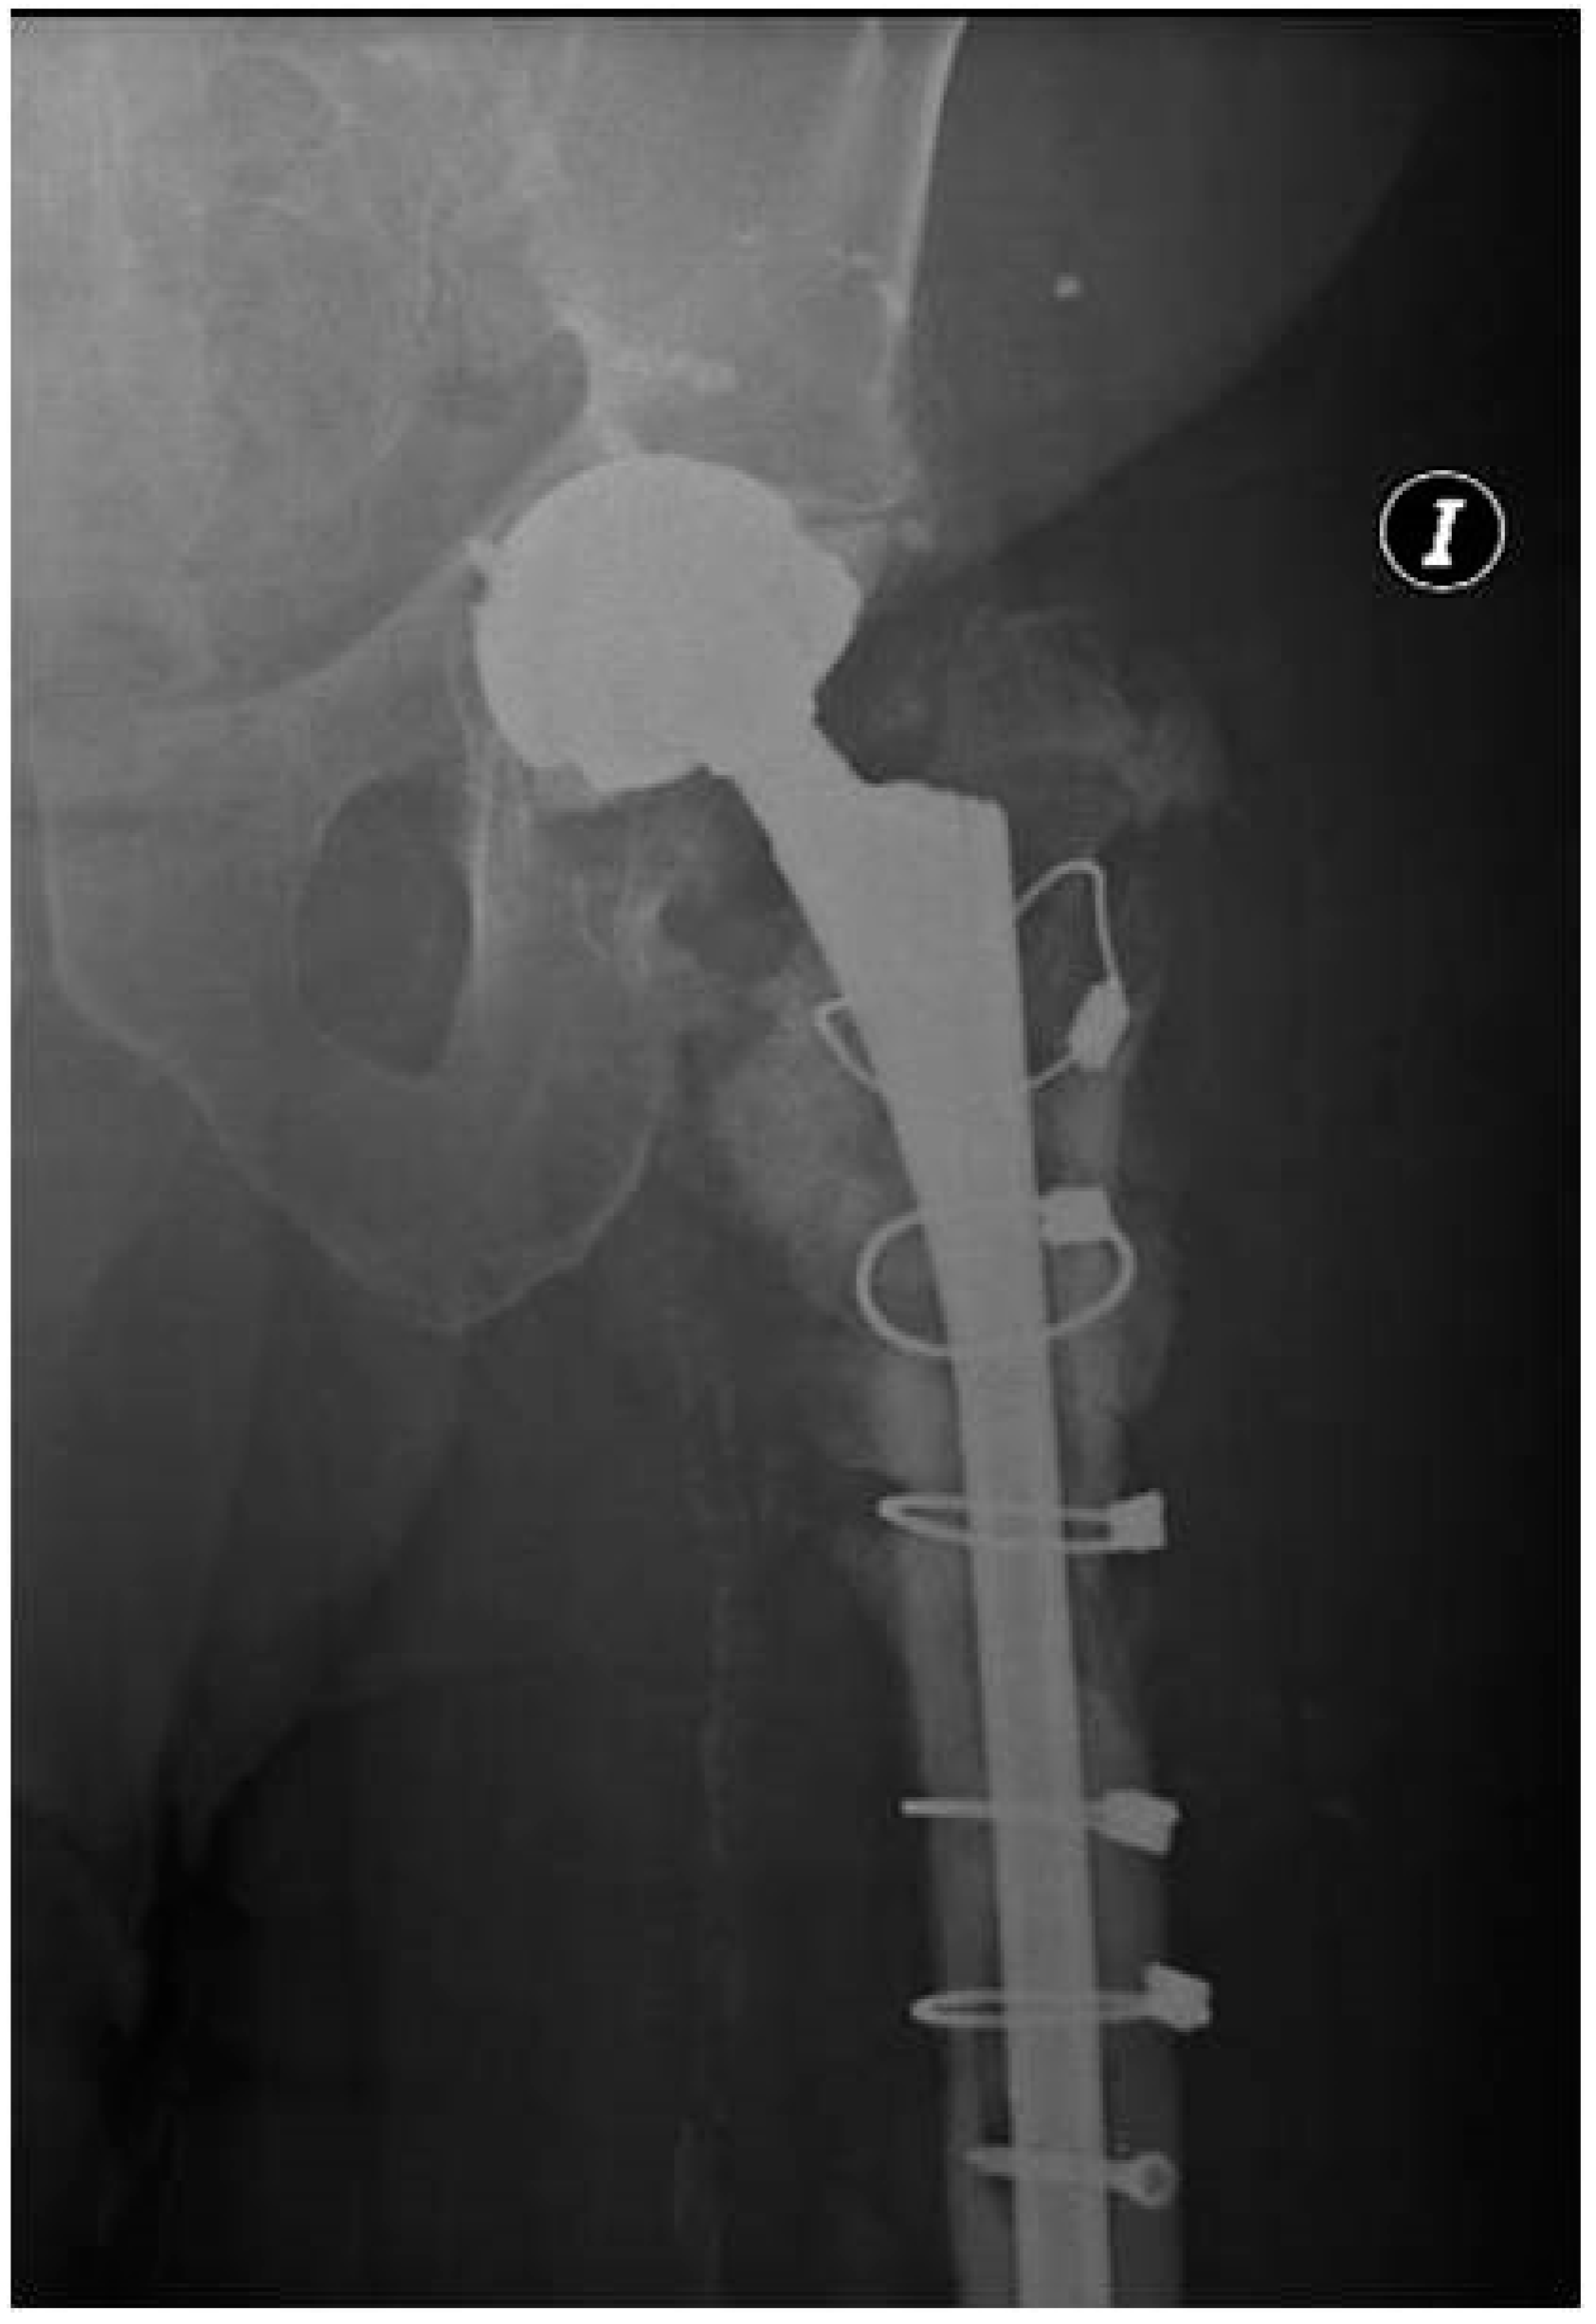

One-Stage Hip Revision Arthroplasty Using Megaprosthesis in Severe Bone Loss of The Proximal Femur Due to Radiological Diffuse Osteomyelitis

2.1. Case 1

2.2. Case 2